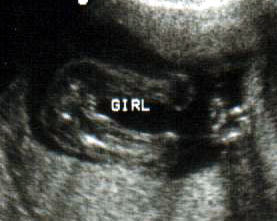

ثانيا : البنت

الاسبوع ال16

الاسبوع ال17